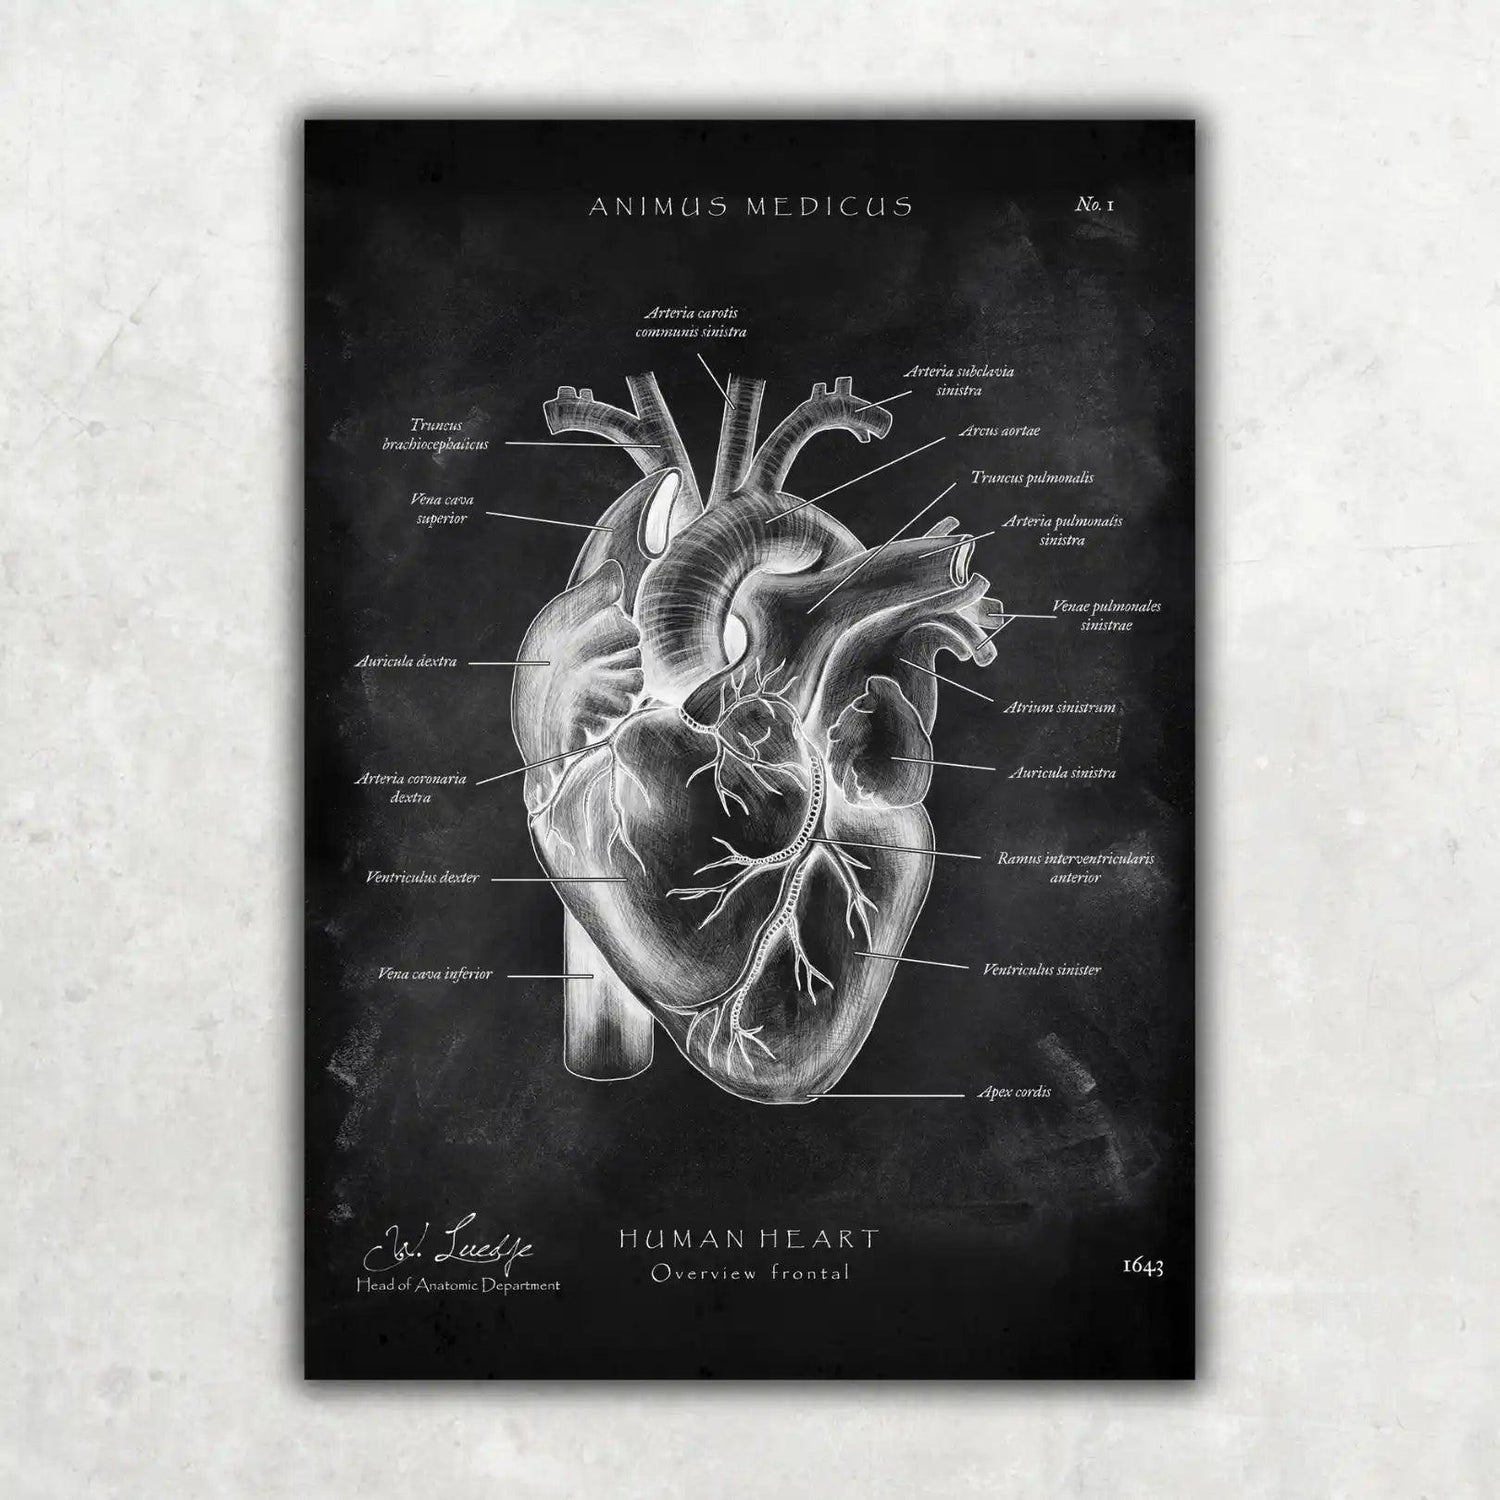

Warst du auf der Suche nach einer Möglichkeit, die faszinierende Anatomie des Herz-Kreislauf-Systems nicht nur zu lernen, sondern auch visuell zu erleben? Bei Animus Medicus findest du ästhetische Anatomie-Poster im Vintage-Stil, die medizinisches Wissen und kunstvolles Design perfekt vereinen. Entdecke jetzt unsere Kollektionen auf https://animus-medicus.de und bringe die Schönheit der Anatomie an deine Wände.